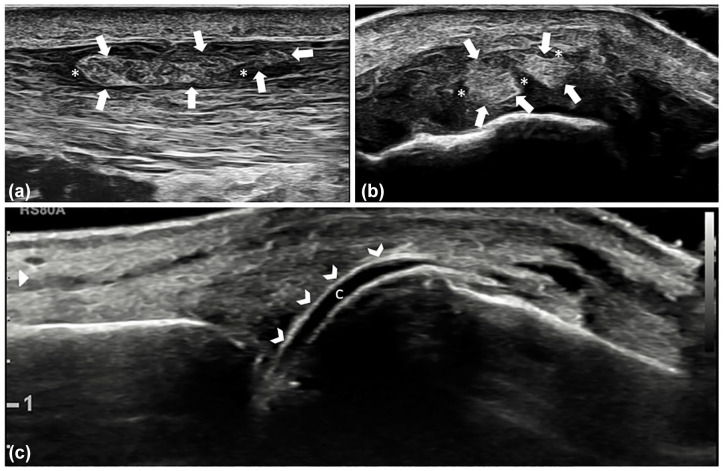

痛风和焦磷酸钙沉积症(CPPD)是晶体性关节炎最常见的病因。确定致病晶体沉积是诊断的基石,同时也是预后和疾病监测的基础。几十年来,传统的放射成像一直是唯一使用的成像技术,但其对这两种疾病的敏感性非常有限。超声波和双能计算机断层扫描(DECT)等先进技术正越来越多地应用于痛风和CPPD疾病的诊断和管理中,它们在分类标准和诊治建议中的作用现已得到广泛认可。在痛风中,单钠尿酸盐沉积的超声基本病变已得到明确定义,并已被证明对变化敏感,可对其进行监测,而 DECT 可对这些沉积物进行直接量化。在 CPPD 疾病中,超声对基本病变的定义及其评分已经非常明确,而 DECT 可以帮助在其他含钙结构中鉴别焦磷酸钙晶体沉积物的概念也已得到证实。本综述旨在概述先进成像技术在晶体诱发的关节病中的应用。

Gout and calcium pyrophosphate deposition (CPPD) disease are the most common causes of crystal arthritis. Identifying the pathogenic crystal deposition is the cornerstone of the diagnosis, but also prognosis and monitoring of the diseases. Conventional radiography has been for decades the only imaging technique used, with its very restricted sensitivity in both diseases. Advanced techniques, namely ultrasound and dual-energy computed tomography (DECT), are being increasingly used in the diagnosis and management of gout and CPPD diseases, and their role is now well recognized in classification criteria and in recommendations for the diagnosis and management. In gout, ultrasound elementary lesions of monosodium urate deposition are well defined and have been shown to be sensitive to change and can be monitored, while direct quantification of these deposits can be performed with DECT. In CPPD disease, the definition of elementary lesions and their scoring has been well established for ultrasound, while the proof of concept that DECT can help discriminate calcium pyrophosphate crystal deposits among other calcium-containing structures has been shown. The aim of this narrative review is to provide an overview of the use of advanced imaging techniques in crystal-induced arthropathies.